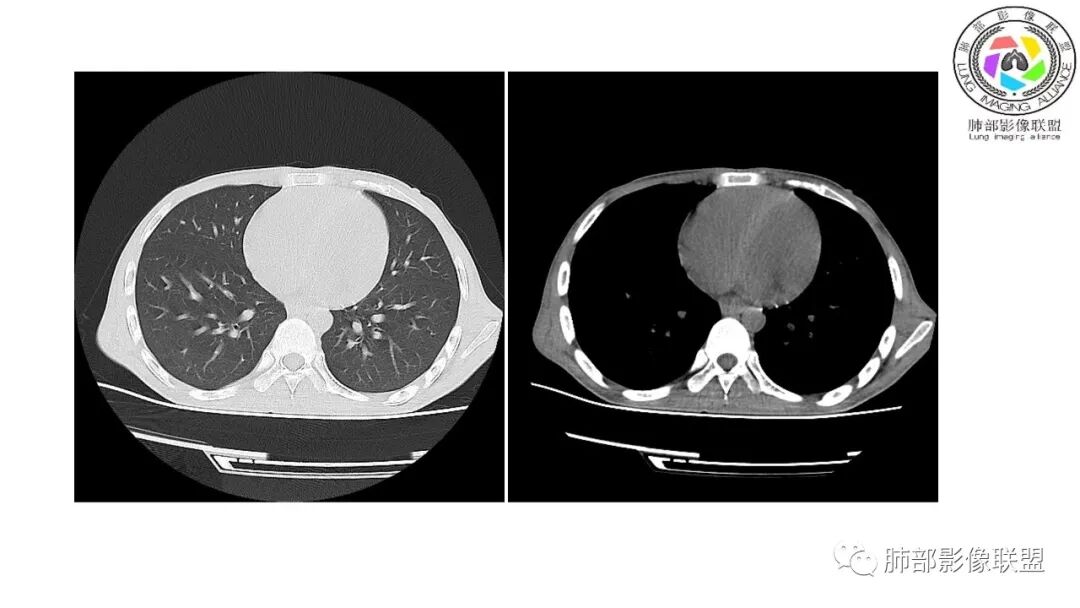

影像与临床:1.青年男性,HlV阳性,颜面部皮疹(未提供皮疹图像)、发热(高热),实验室CRP、PCT高,T-Spot阴性。2.右肺下叶空洞结节,壁厚不均,边界清楚,其内线状影,未见液平及钙化,未见卫星灶,纵隔淋巴结增大,双侧腋窝见增大淋巴结。心腔内低密度提示贫血可能。肝脾影增大,未见结节影及块影。腹膜后见多发增大淋巴结。

综合分析:本例肺部影像学改变并不具有特征性,空洞性病灶须与多种疾病鉴别,但年轻HIV阳性患者,高热,皮疹,肝脾增大,纵隔、腋窝、腹膜后见多发增大淋巴结等都强烈提示马尔尼菲篮状菌感染的可能性。

马尔尼菲青霉菌病(Penicilliosis Maneffei,PSM) 是由马尔尼菲青霉菌(Penicillium Mane&i,PM)感染引起的一种致死性深部真菌病,PM主要侵犯单核巨噬系统,可表现为局灶性和播散性感染,在免疫功能低下的感染者中,死亡率高。该菌是由Capponi1956年从越南野生中华竹鼠肝脏中首次分离出并命名。该病主要流行于东南亚一带,在我国以广西广东多见。有文献研究中国大陆1984年到2009年感染马尔尼菲青霉菌668例患者中有99.4%病例发生在中国南部,以广西广东为主,有87.7%病例发生在艾滋病患者中,有3.8%的病人发生在其它免疫抑制患者中,有8.5%发生在免疫功能正常者。PM的传播途径尚不明确,公认的主要传播途径有呼吸道,消化道,外伤等,亦不除外接触孢子污染的土壤而感染。马尔尼菲青霉菌病的常见的临床表现为发热,贫血,消瘦,呼吸道症状,皮肤损害,肝脾肿,淋巴结肿大。播散型PSM常累及肺,皮肤,网状内皮系统(包括骨,骨髓,关节,淋巴结,心包,肝脾)。不同宿主状态下PSM临床表现也有不同,HIV阳性患者主要表现为持续性发热,软疣状皮肤损害,血培养阳性率高,白细胞正常或偏低等。HIV阴性患者主要表现为间歇发热,皮下结节和脓肿,淋巴结肿大,骨痛溶骨,白细胞增高等。马尔尼菲青霉病的诊断主要靠沙氏琼脂培养基25℃及37℃环境下可培养出PM(金标准)。马尔尼菲青霉菌肺部表现具有多样性,可以表现为实质改变、间质改变、纵隔淋巴结肿大、胸膜改变及气管改变。有文献报道马尔尼菲青霉菌病患者82.7%胸部CT有异常改变,胸部CT表现:45.6%患者肺野斑片状浸润阴影或局限性肺实变,11.9%患者表现为结节影,11.5%患者表现为毛玻璃改变,8.4%患者表现为弥漫性粟粒样病变,5.3%患者表现为结节状肿块影。45.1%患者胸部影像学伴肺门或纵隔淋巴结肿大,23.5%患者伴胸腔积液,8.0%伴空洞病灶。参考文献:张建全, 杨美玲, 钟小宁, 等. 人免疫缺陷病毒抗体阴性与阳性者播散性马尔尼菲青霉菌病的临床及实验室特征[J]. 中华结核和呼吸杂志, 2008, 31(10):740-746.张云桂,赵月娟,李玉叶,等.226例艾滋病合并马尔尼菲青霉菌病患者的影像学特征[J]. 皮肤病与性病,2016, 38(2):91-94.